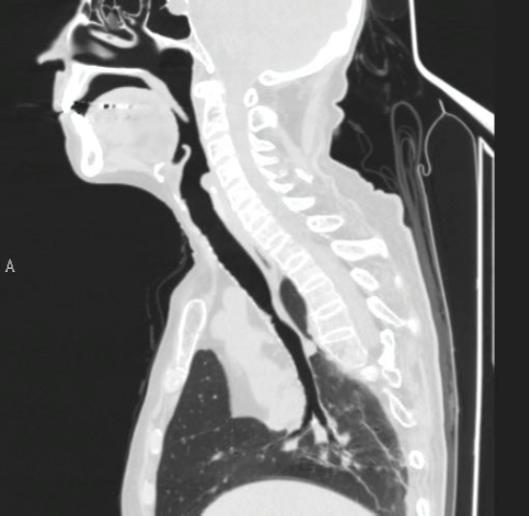

-Tomografía cervicotorácica con reconstrucción del árbol traqueobronquial, importante para el planeamiento del tratamiento.